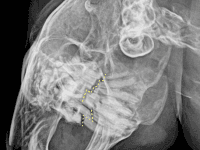

犬 2026年4月21日 犬の血尿・頻尿の原因。膀胱結石の摘出手術 犬が何度もトイレに行く、尿に血が混じる、おしっこが出にくそうにしている。このような症状が見られる場合、「膀胱炎」や「膀胱結石」が疑われます。血尿や頻尿症状がある時にはエコー検査やレントゲン検査、尿検査等を実施し原因を調べ […]